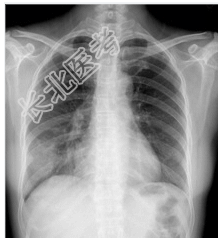

- [材料题] 患者,女性,35岁,发热、咳嗽5天,咳嗽时伴有右侧胸痛。查体:右下肺可闻及湿啰音,心脏体查无异常。做胸部X光平片检查。

- 简答题1、诊断及依据是什么?

- 简答题2、鉴别诊断有哪些?